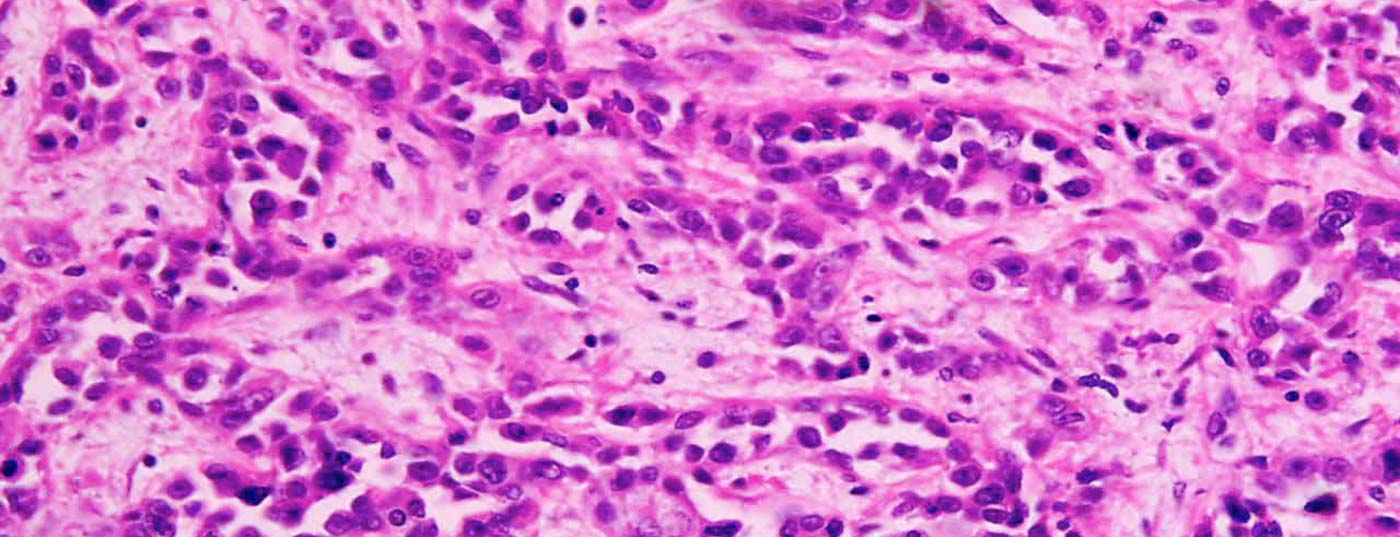

Im Rahmen des Krebsgenom-Atlas-Projekts, das sämtliche Gendefekte bei allen bekannten Krebsarten identifiziert, wurde kürzlich eine neue molekulargenetische Einteilung des Magenkarzinom in vier Subtypen vorgeschlagen. Diese Typisierung soll künftig neue Ansätze für zielgerichtete molekulargestützte Therapien ermöglichen. An der Jahrestagung der Deutschen, Österreichischen und Schweizerischen Gesellschaften für Hämatologie und Medizinische Onkologie wurden neue Therapieoptionen diskutiert.